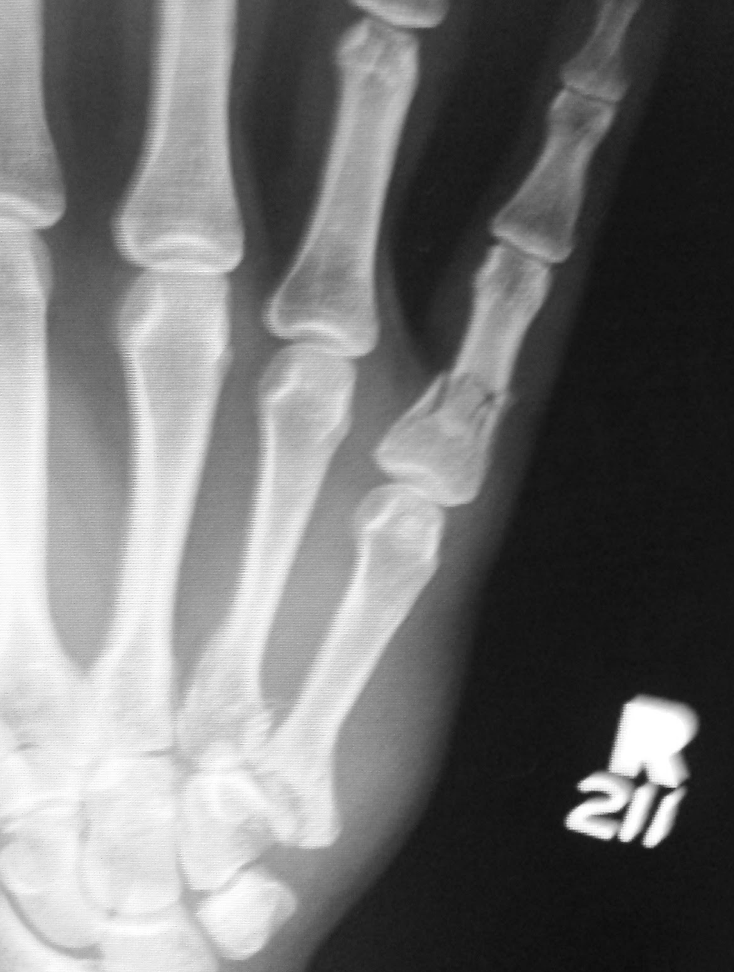

Remember how I was bitching and moaning about how rim brakes suck in the rain? Well, in the dry, the combination of Kool-Stop Salmon pads plus Michelin Pilot City tires = instant endo when you slam on the brakes while standing on the pedals in response to a pedestrian stepping out in front of you on 40th st.

On the plus side, I didn't land under the wheels of the bus that was beside me. On the minus side, I'm now a leftie. And of course this had to happen three days before Nicole and I are moving into our new house...